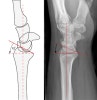

* Palmar tilt(=Volar tilt)

Represents the saggital plane inclination of the distal radial articular surface.